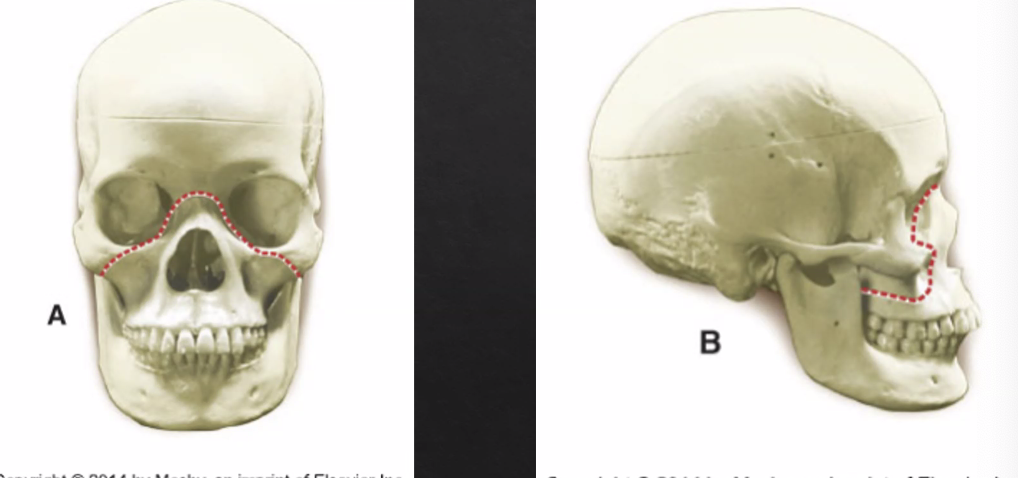

LeFort I

horizontal fracture of maxilla

least amount of force to cause fracture

LeFort II

pyramidal horizontal

fracture of maxilla and nose

LeFort III

craniofacial disjunction

bone is not stabilized and is mobile

face not attached to cranium

fracture near orbits

least common injury, with extreme force needed to occur